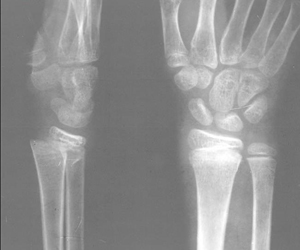

骨折

確定有骨折后,一定要對(duì)傷肢(指)作固定再送醫(yī)院,否則骨折斷端異常活動(dòng),會(huì)加重?fù)p傷。可因地制宜用木板、木棍、樹枝、竹竿、雜志等作為固定用的臨時(shí)夾板。若無上述材料,可將上肢固定在軀干上,下肢固定在對(duì)側(cè)的健肢上。